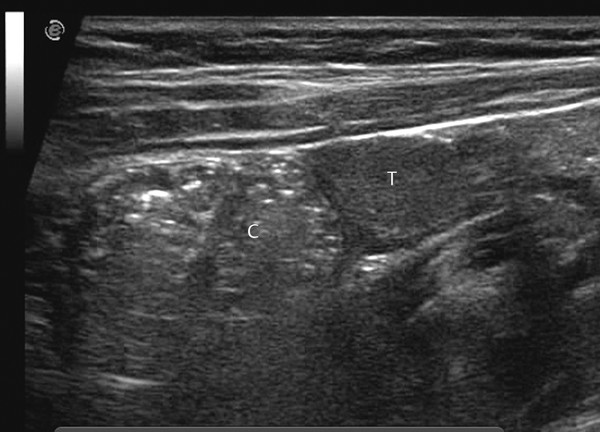

Male Genital Injuries